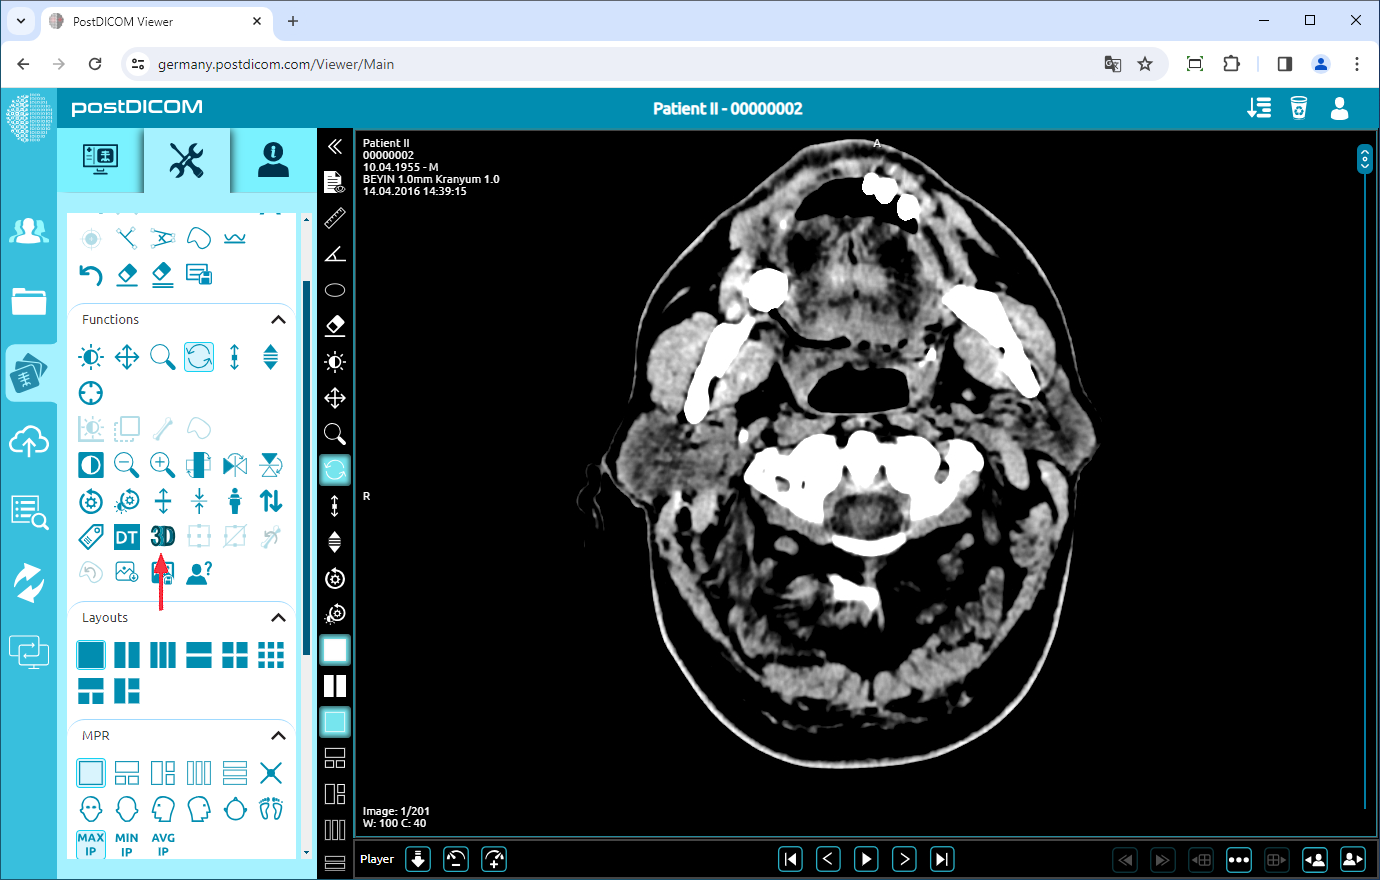

After you have clicked, the tools section will be displayed. In the functions field, click on the “3D View” icon on the left side of the field.